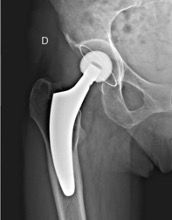

Hips in coxa vara sometimes present a very significant femoral offset which may be prove to be difficult to restore using standard stems. In this case, a varus-tilted or lateralized stem should be used and this will require a very low femoral cut, often with loss of residual femoral offset and a risk of lengthening the lower limb. Positioning a straight cementless stem in varus runs the risk of trajectory error and femoral pain. If a modular neck implant is chosen, the increased lever arm results in significant pressures on the modular neck and neck-head junction with risks that are already known. Finally, even with a cemented stem, positioning it in varus will increase the pressures on the bone-cement interface, with a risk of early loosening. With calcar-guided short stems, the stem will follow the medial cortex of the neck (which will have been cut high), naturally finding a varus tilt and making it possible to reproduce even very significant offsets (Figs 4 and 5).

In total hip replacement, there is often a relative reduction in the acetabular offset due to burring off a few millimetres, which is necessary for the implant to fit in the hip socket cavity, and this is compensated for by a relative increase in femoral offset, to restore the overall hip offset.